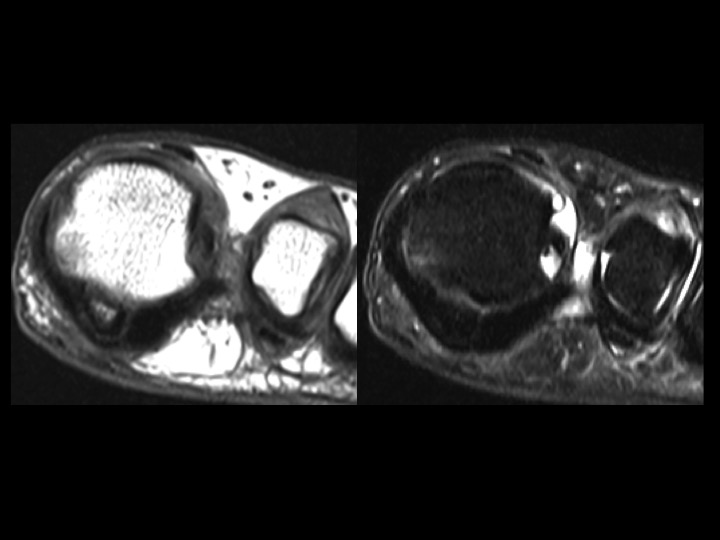

31F 5 years pain, evaluate sesamoid AVN

In the AP XR, the fibular sesamoid is not visible, but in the sesamoid view, its diminutive, smooth and not sclerotic. This leads me to believe that this is marked hypoplasia rather than AVN. Hallucal sesamoid variants are common. Aplasia is uncommon. Hypoplasia is not rare, but this degree of hypoplasia seems unusual. Based on the images, it seems there is compensatory thickening of the fibular portion of the plantar plate (sesamoids are embedded in the plantar plate). Structures stay where they are supposed to be: the tibial sesamoid is located and the FHL is midline in the short axis image. Shes had pain for 5 years....which I cannot explain, other than to say that normal variants may be symptomatic. The attached article is a little crazy, check it out. Reference article.